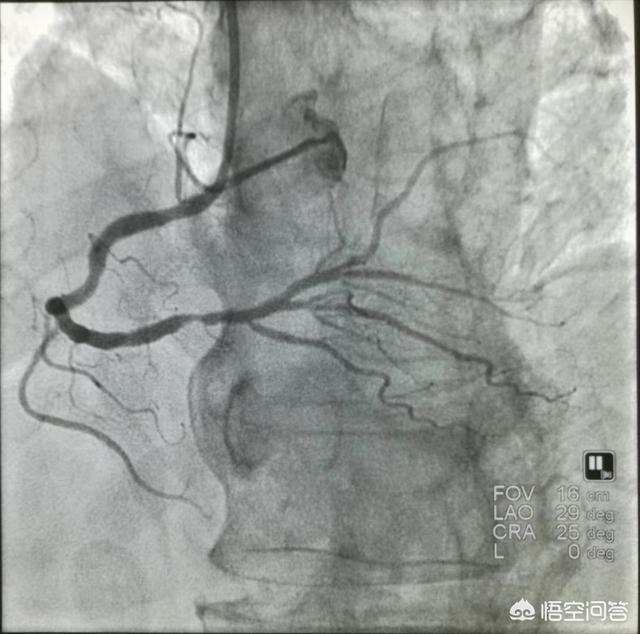

Nous savons tous que la coronarographie est l'examen de référence pour le diagnostic des maladies coronariennes, mais il s'agit après tout d'un test invasif, nous ne pouvons pas l'appliquer simplement au patient, quels que soient le moment et la nature de la maladie, il est nécessaire de la diagnostiquer en intégrant de multiples conditions, et le premier diagnostic des patients atteints de maladies coronariennes est le symptôme, et l'apparition de la douleur, les facteurs déclenchants, le moment et la nature de la douleur sont tous d'une grande importance, et nous pouvons fondamentalement exclure une partie des patients en analysant le symptôme, puis le symptôme. Une fois que tous les tests indiquent la présence d'une maladie coronarienne, ce n'est qu'à ce moment-là que nous devons procéder à une coronarographie pour préciser le site et le degré de la sténose et confirmer le diagnostic de maladie coronarienne.

Diagnostic de la maladie coronarienne